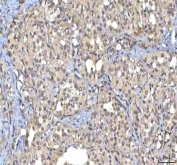

IHC staining of FFPE human rectum adenocarcinoma tissue with RASGRP3 antibody. HIER: boil tissue sections in pH8 EDTA for 20 min and allow to cool before testing.

IHC staining of FFPE human breast cancer tissue with RASGRP3 antibody. HIER: boil tissue sections in pH8 EDTA for 20 min and allow to cool before testing.

IHC staining of FFPE human lung cancer tissue with RASGRP3 antibody. HIER: boil tissue sections in pH8 EDTA for 20 min and allow to cool before testing.

IHC staining of FFPE human thyroid cancer tissue with RASGRP3 antibody. HIER: boil tissue sections in pH8 EDTA for 20 min and allow to cool before testing.